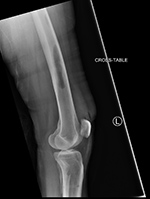

43 year-old man with comminuted right tibia and fibula fractures as well as extensive bone loss and soft tissue injury. A tibial intramedullary nail with proximal and distal locking screws is present as well as multiple rounded bony allografts. There are also large skin staples.